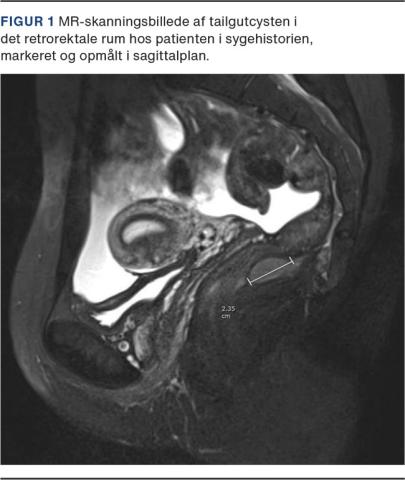

En 30-årig kvinde henvendte sig i den kirurgiske akutmodtagelse med perianale smerter. I forbindelse med udredning og akut behandling for en perianal absces og efterfølgende fistelproblematik blev der påvist en tailgutcyste ved hhv. endoanal ultralyd- (EAUL) og MR-skanning (Figur 1). Der var ingen kommunikation til fistlen, og efter behandling af patientens absces- og fistelsygdom var der persisterende intermitterende smerter rektalt samt urogenitale gener, som man konkluderede måtte stamme fra cysten. Cysten målte 2,3 × 2,1 cm og var beliggende 9 cm oralt for den anokutane overgang i det retrorektale rum. På grund af den tarmnære lokalisation og den beskedne størrelse valgtes kirurgisk excision med TEM. Cysten blev excideret in toto via longitudinel adgang i den posteriore midtlinje i rectum, og kaviteten blev lukket primært med V-Loc-sutur. Patienten blev udskrevet velbefindende den følgende morgen. Ved afsluttende kontrol tre måneder senere angav patienten sig smertefri, og ved EAUL konstateredes hun recidivfri. Histologisk undersøgelse bekræftede diagnosen, og der fandtes frie resektionsrande.